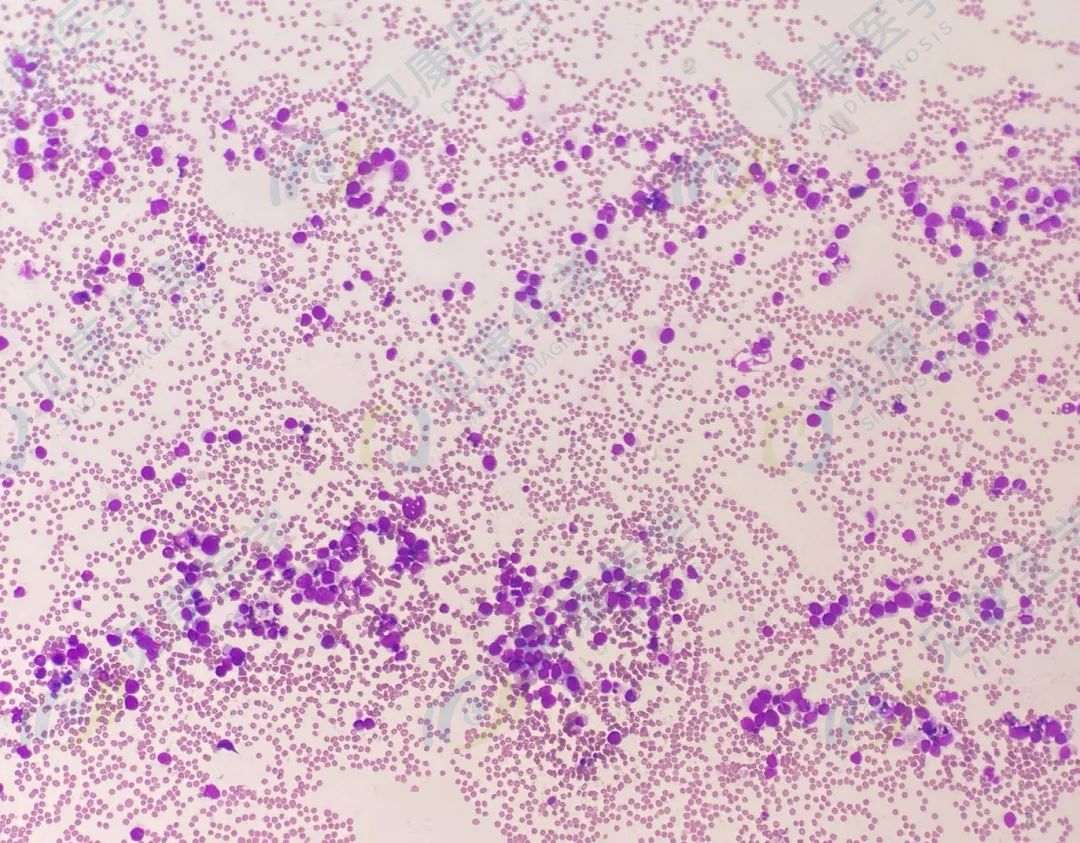

【形态学病例分享】第五十八期

男,58岁,乏力2月余,鼻出血4天。

血常规:

HB 50g/L

骨髓涂片

骨髓转移癌

田欣 王占龙 陈雪晶 李晓艳